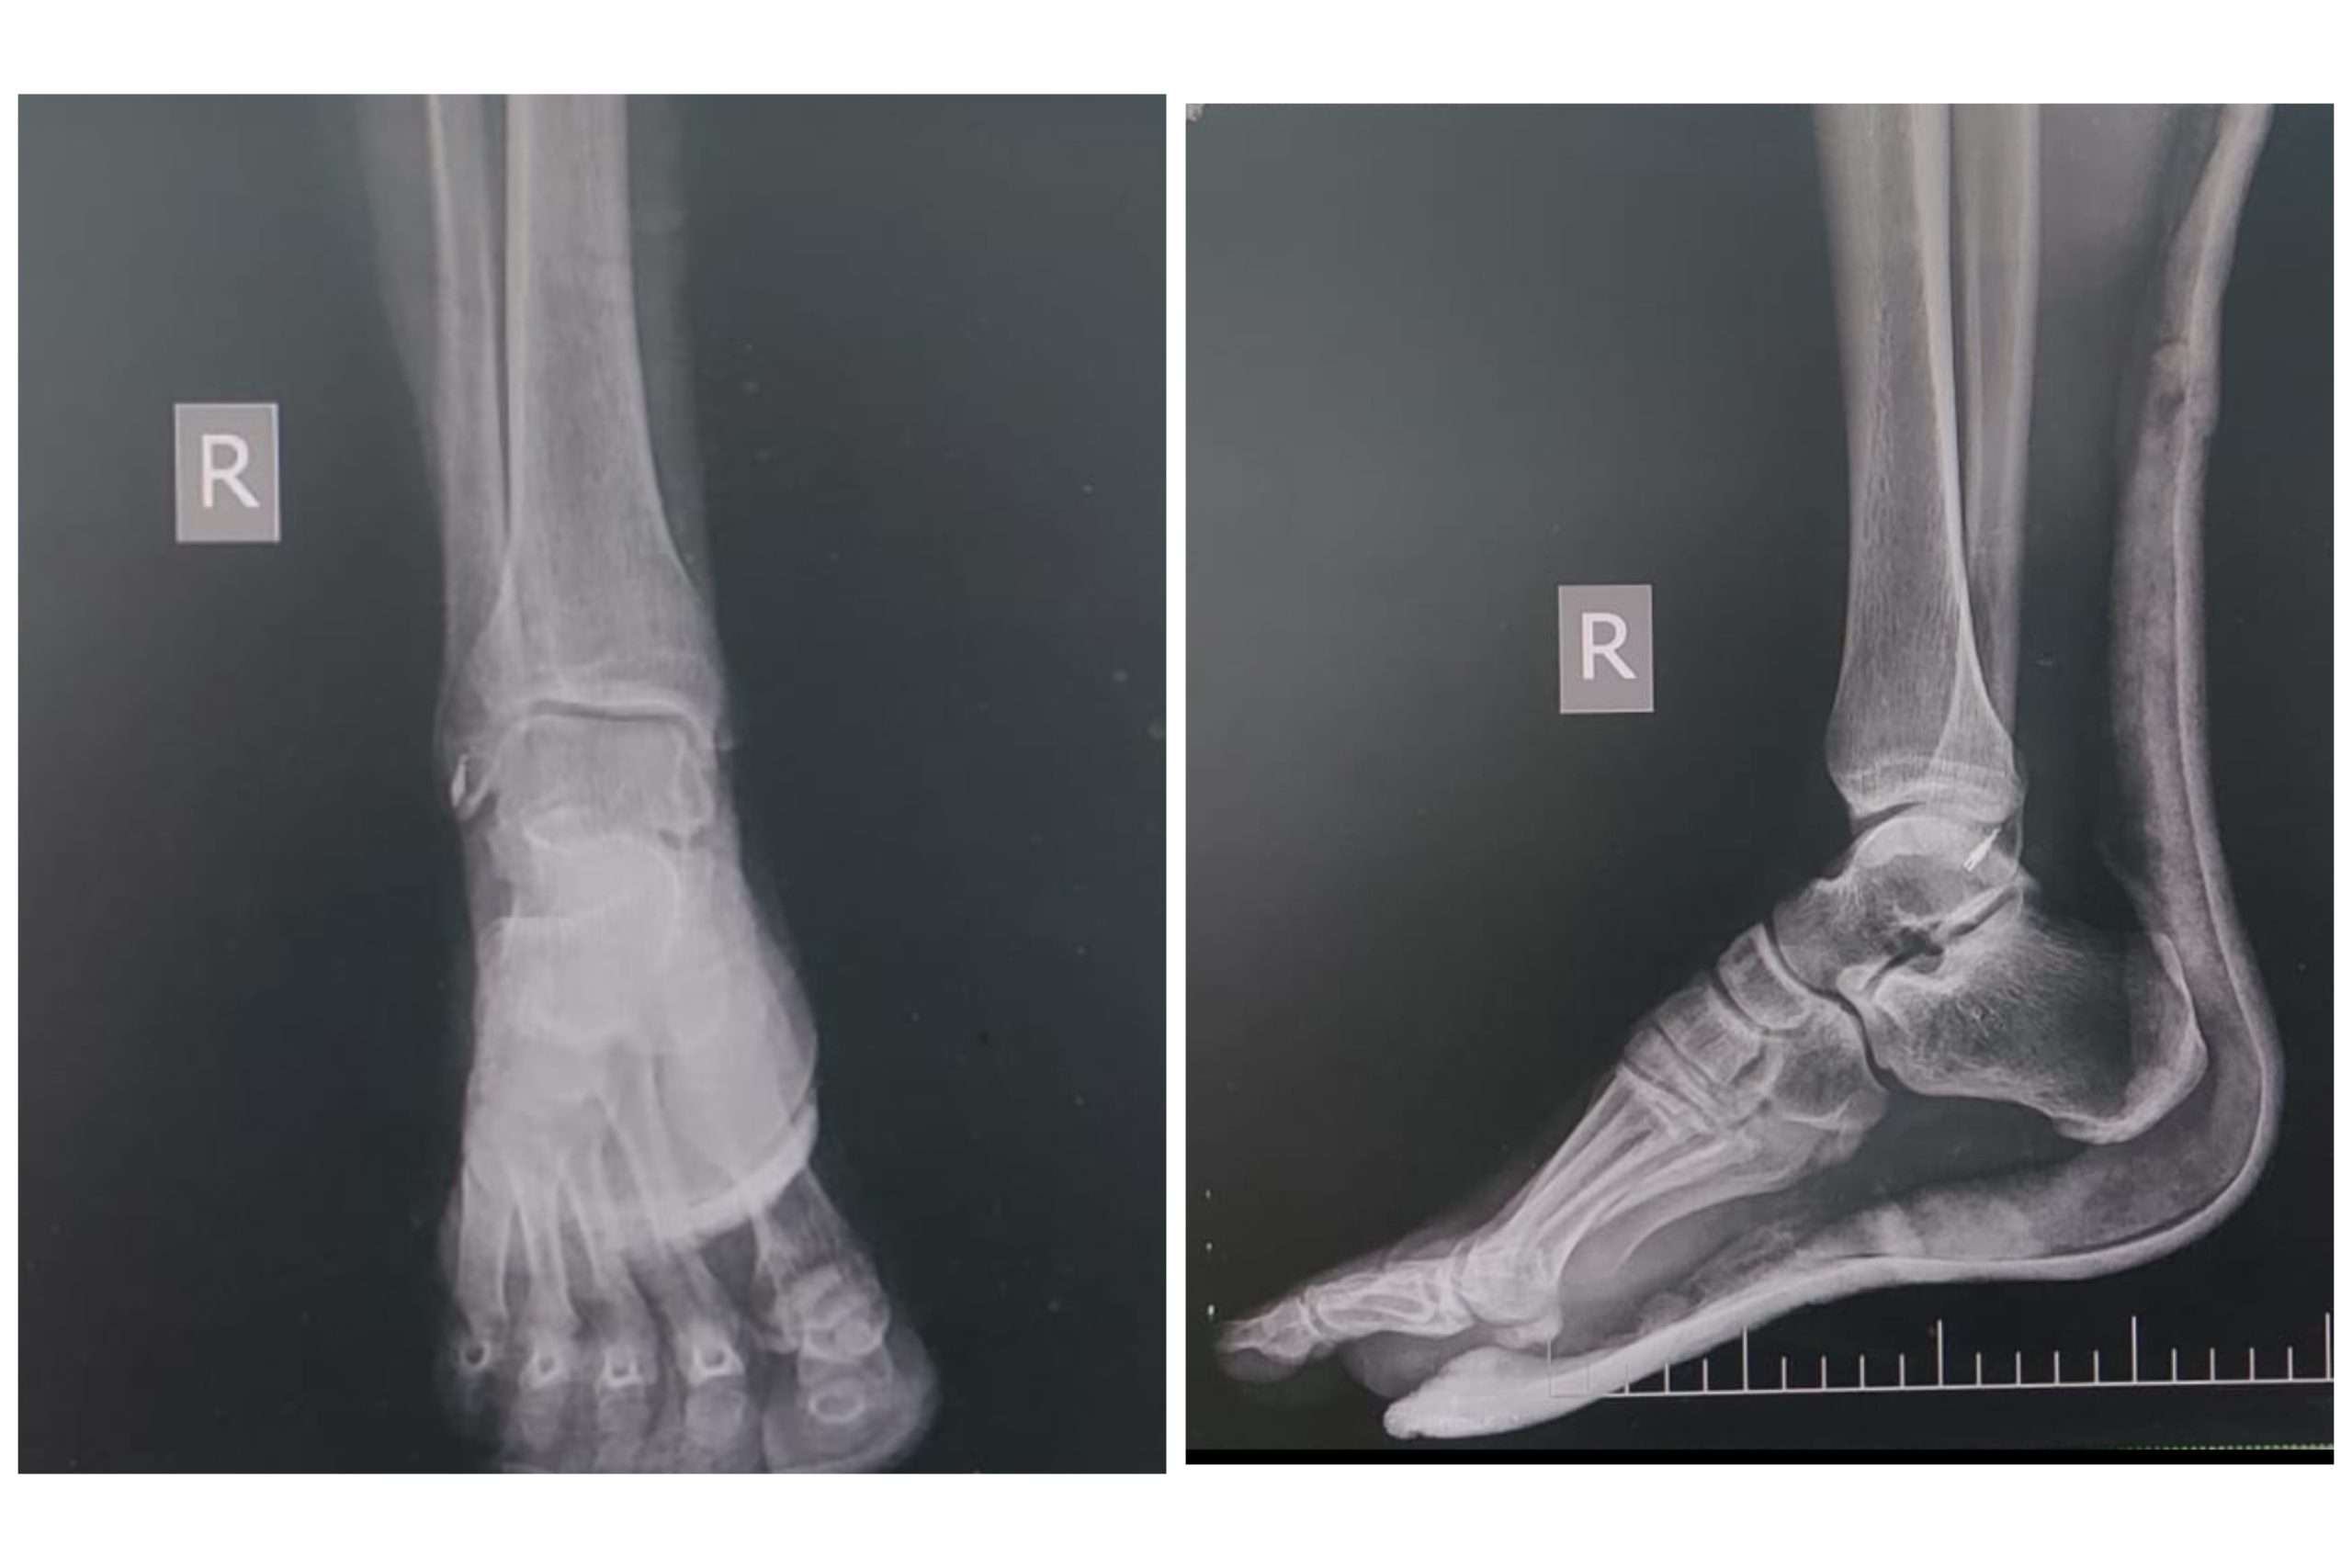

Малоберцово-большеберцовый сустав (также называемый тибио-фибуло-талачной или калканео-фибуло-голеностопным суставом) представляет собой сложную соединительную структуру, которая соединяет голень с стопой. В этом суставе участвуют две крупные кости, голень (тибия и фибула), а также кости стопы — таранная кость и неподалеку расположенные мелкие костные образования.

Кости, формирующие сустав

Давайте разберемся, из каких костей состоит этот сложный сустав:

| Кость | Роль в составе сустава | Особенности |

|---|---|---|

| Тибия (голень) | Основная несущая и стабилизирующая кость в суставе | Форма с плоским верхним концом, формирует одну из основных опор |

| Фибула (малоберцовая кость) | Обеспечивает боковую стабилизацию и поддержку | Работает в паре с большеберцовой костью, относительно тонкая |

| Таранная кость (астигма) | Соединяет голень с костями стопы | Ключевое соединение, позволяющее стопе сгибаться и разгибаться |

| Малоберцовая кость стопы и другие мелкие кости | Строят основание для движений стопы и помогают в амортизации | Они соединяются с большеберцовой и таранной костью |

Связки и суставные поверхности

Для нормального функционирования сустава важны не только кости, но и связки, соединяющие их. Основные связки включают:

- Передняя таранно-малоберцовая связка — стабилизирует переднюю часть сустава

- Задняя таранно-малоберцовая связка — укрепляет задний отдел сустава

- Латеральные связки — обеспечивают боковую стабильность

- Медиальные связки — удерживают сустав в правильном положении

Суставные поверхности покрыты hyaline cartilage, что снижает трение при движениях и способствует амортизации нагрузок.

Особенности строения при травмах и патологиях

Одна из важнейших причин обращения к специалисту — травмы в области данного сустава. Наиболее часто — растяжения связок, вывихи, переломы костей, а также дегенеративные изменения.

| Тип травмы | Описание | Пути лечения |

| Растяжение связок | Повреждение связочного аппарата вследствие чрезмерных нагрузок | Иммобилизация, физиотерапия, реабилитация |

| Вывих | Выход костей за пределы сустава | Вправление, фиксация, последующая реабилитация |

| Перелом | Разрыв или трещина костей | Операция или консервативное лечение с гипсовой фиксацией |

| Дегенеративные процессы | Износ хрящей и связочного аппарата со временем | Медикаментозное лечение, физиотерапия, хирургия в тяжелых случаях |